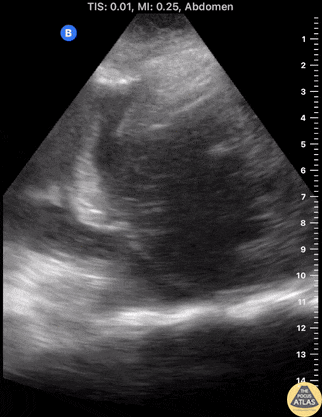

Biliary - Pyogenic Liver Abscess with Pleural Effusion

A elderly female with severe sepsis with E. coli bacteremia initially thought to be from urinary source developed worsening hypoxia overnight. Using a Butterfly US, a moderate-sized right pleural effusion with associated ~6cm liver abscess is seen. These images helped mobilize pulmonology and IR to place a chest tube and hepatic drain, which led to resolution of hypoxemia and sepsis. Hepatic drain cultures grew E coli. Although one may appreciate a diaphragmatic defect on the image, the pleural fluid remained sterile. POCUS in this case led to successful identification of the true sepsis source and associated pleural effusion as a complication of pyogenic liver abscess. Contributors: Eric Reid, MD